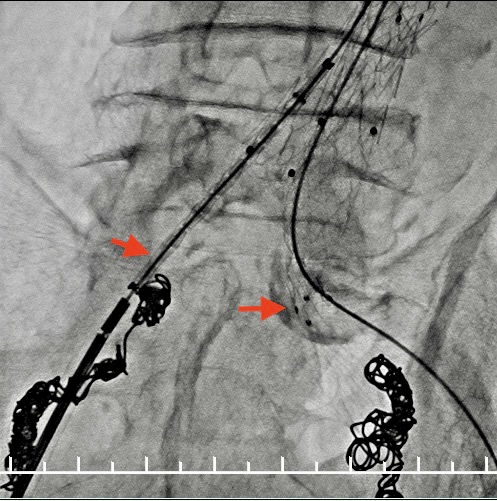

栓塞右侧髂内动脉,角度刁钻,使用翻山桥配合猪尾导管及超滑眼镜蛇,到达靶血管。8mm、6mm弹簧圈栓塞。

栓塞左侧髂内动脉。箭头处可见髂总动脉钙化扭曲明显,进出导管十分困难。